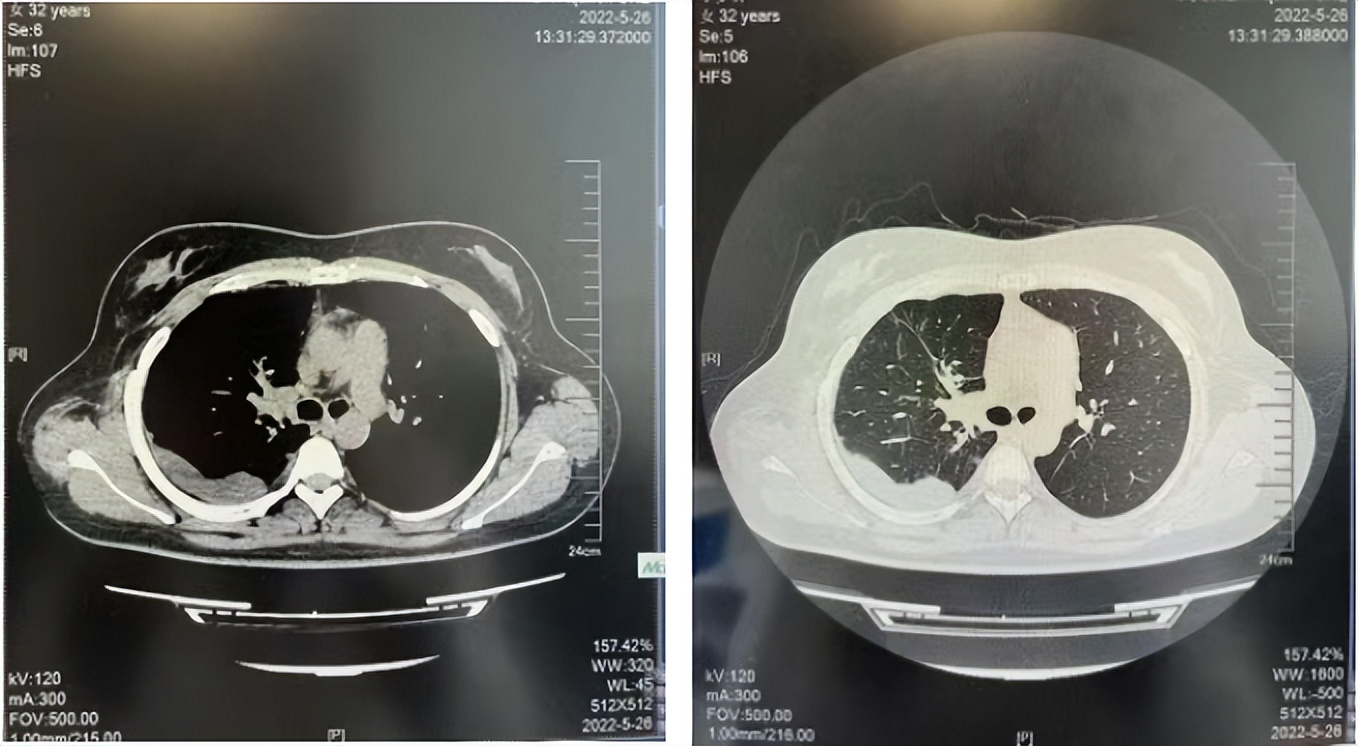

56岁,女性,无吸烟史饮酒史,既往体健。2023年02月患者体检发现肺占位性病变,胸部增强CT:右肺下叶后基底段结节;右侧锁骨上及纵隔内多发淋巴结肿大。PET-CT:右肺下叶周围型肺癌可能性大;1R、2L、3P、4R、4L及7组淋巴结转移可能性大。2023年02月就诊于本院胸外科行超声胃镜下纵隔肿物穿刺活检术,病理:结合免疫组化,符合肺腺癌。行NGS基因检测:EML4:exon20-ALK:exon20融合。PD-L1(克隆号22C3)TPS=55%。

治疗经过:2023年3月27日始行恩沙替尼靶向治疗至今,最佳疗效为PR,末次评效为维持PR。期间出现轻度肝功能异常(DILI 1级),对症处理后好转。截止目前PFS为26个月。

2023年2月20日基线检查

2024年6月复查PR(最佳疗效)

2024年12月复查维持PR

2025年3月复查维持PR